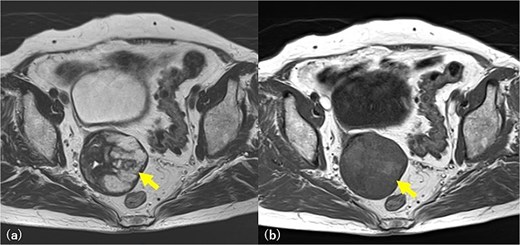

A 78-year-old woman (gravida 3, para 2), with hypertension and hyperlipidemia, was receiving medical treatment. She had undergone an appendectomy at 13 years, surgery for an ectopic pregnancy at 23 years, and a total hysterectomy at 40 years, all via laparotomy. Details of the hysterectomy were unavailable owing to the long interval. Nine years earlier, abdominal computed tomography (CT) performed for a pancreatic cyst incidentally revealed a right pelvic mass. Contrast-enhanced magnetic resonance imaging (MRI) showed a 4.5 cm lesion, with mixed signal intensity on T2-weighted imaging and mild peripheral enhancement, leading to a preoperative diagnosis of a solid ovarian tumor. As she was asymptomatic, conservative follow-up was chosen. Eight years later, MRI showed enlargement of the lesion to 6 cm (Fig. 1), with internal fluid accumulation. An ovarian fibroma, Brenner tumor, or mucinous cyst was suspected. Laparotomy was performed for tumor resection. At the surgery, the retroperitoneal pelvic mass was identified, firmly adherent to the intestine. Central necrotic and fibrotic tissue was observed; however, massive bleeding occurred, and only a biopsy was performed. The operation time was 3 h 33 min, with a blood loss of 1510 g, requiring transfusion of two units of red blood cells and fresh frozen plasma. She was discharged on post-operative Day 9. Histological examination revealed fibrous tissue with cross-sections of gauze fibers and multinucleated giant cell granulomas, confirming gossypiboma (Figs 2 and 3). Given the retroperitoneal location, the lesion was presumed to have originated from gauze retained during a hysterectomy performed 38 years earlier.

Pelvic MRI imaging. A 6 cm diameter solid mass is found in the right pelvic wall and is suspected to be an ovarian fibroma and Brenner tumor. T2-weighted image, a multilocular high signal, and fluid accumulation are revealed (arrow) (a). The same area is slightly detected as a high signal in the T1-weighted image (arrow) (b), and a mucinous tumor is also suspected.